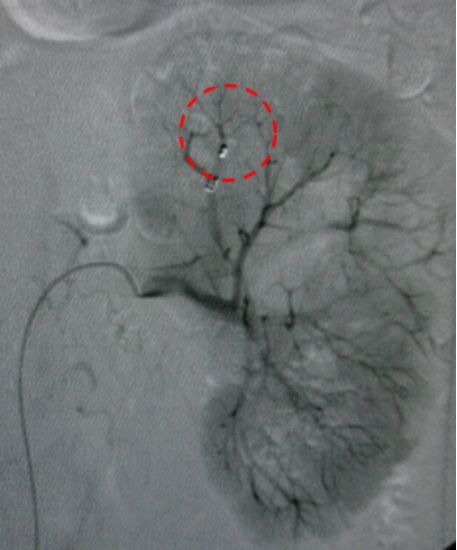

诊断支气管扩张30年,咯血两周。造影发现左右侧支气管动脉迂曲扩张。

治疗前

介入栓塞后,支气管动脉不再向肺内供血,咯血停止。

治疗后